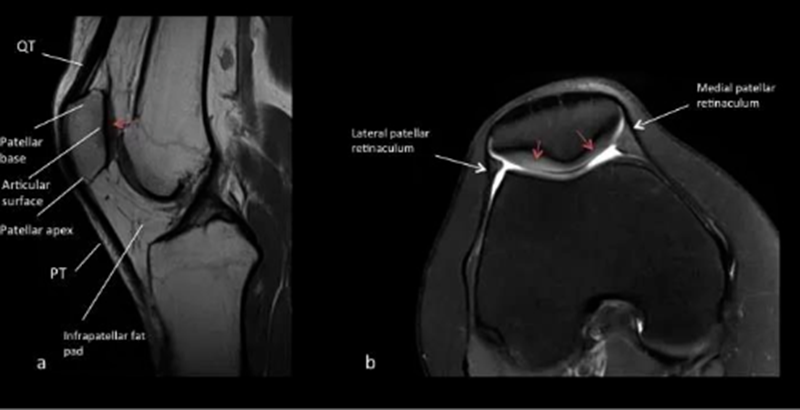

常见影像学检查包括X线、CT和MRI检查。X线早期无异常,直到晚期阶段,如出现广泛的软骨丧失、关节间隙丧失及相关的软骨下骨硬化和囊性变化,X线可诊断。MRI是非侵入性诊断方法,有望在肉眼可见的形态学软骨损失之前检测软骨病变以及软骨内部紊乱的独特功能。

正常MR a.矢状位T1W1 b.横断位T2W1

髌骨软骨软化分级表现